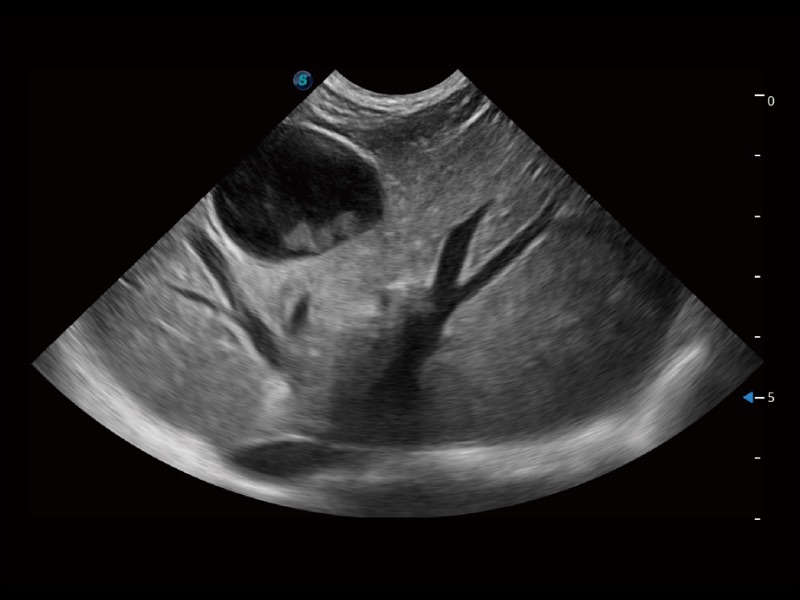

通过创新的 Matrix E自适应滤波器和超长时间域算法,极大提升超低速微细血流的检出能力,同时更精准地滤除软组织和噪声信号,为兽用医生提供以往无法通过常规血流获得的疾病诊断信息。

通过色彩血流和实时宽景相结合,可观察到完整的静脉或动脉的血流,方便医生检查。实时扫查过程中,如有任何操作失误也可以很容易地进行回扫擦除,而不会中断扫查。

ProPet 70专为动物医生设计,对不同的动物体型和生理结构作出了针对性的优化。通过动物影像专用软件,可满足个性化的应用需求,帮助动物医生获得更精确的诊断数据。